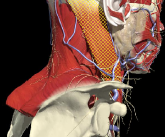

LATEROCAPUT

Muscles that insert into skull (mastoid/ occiput)

- Trapezius

- Sternomastoid

- Splenius capitus/cervicus

- Levator scapulae

- Longissimus capitus

Range of movement

- 8 degrees